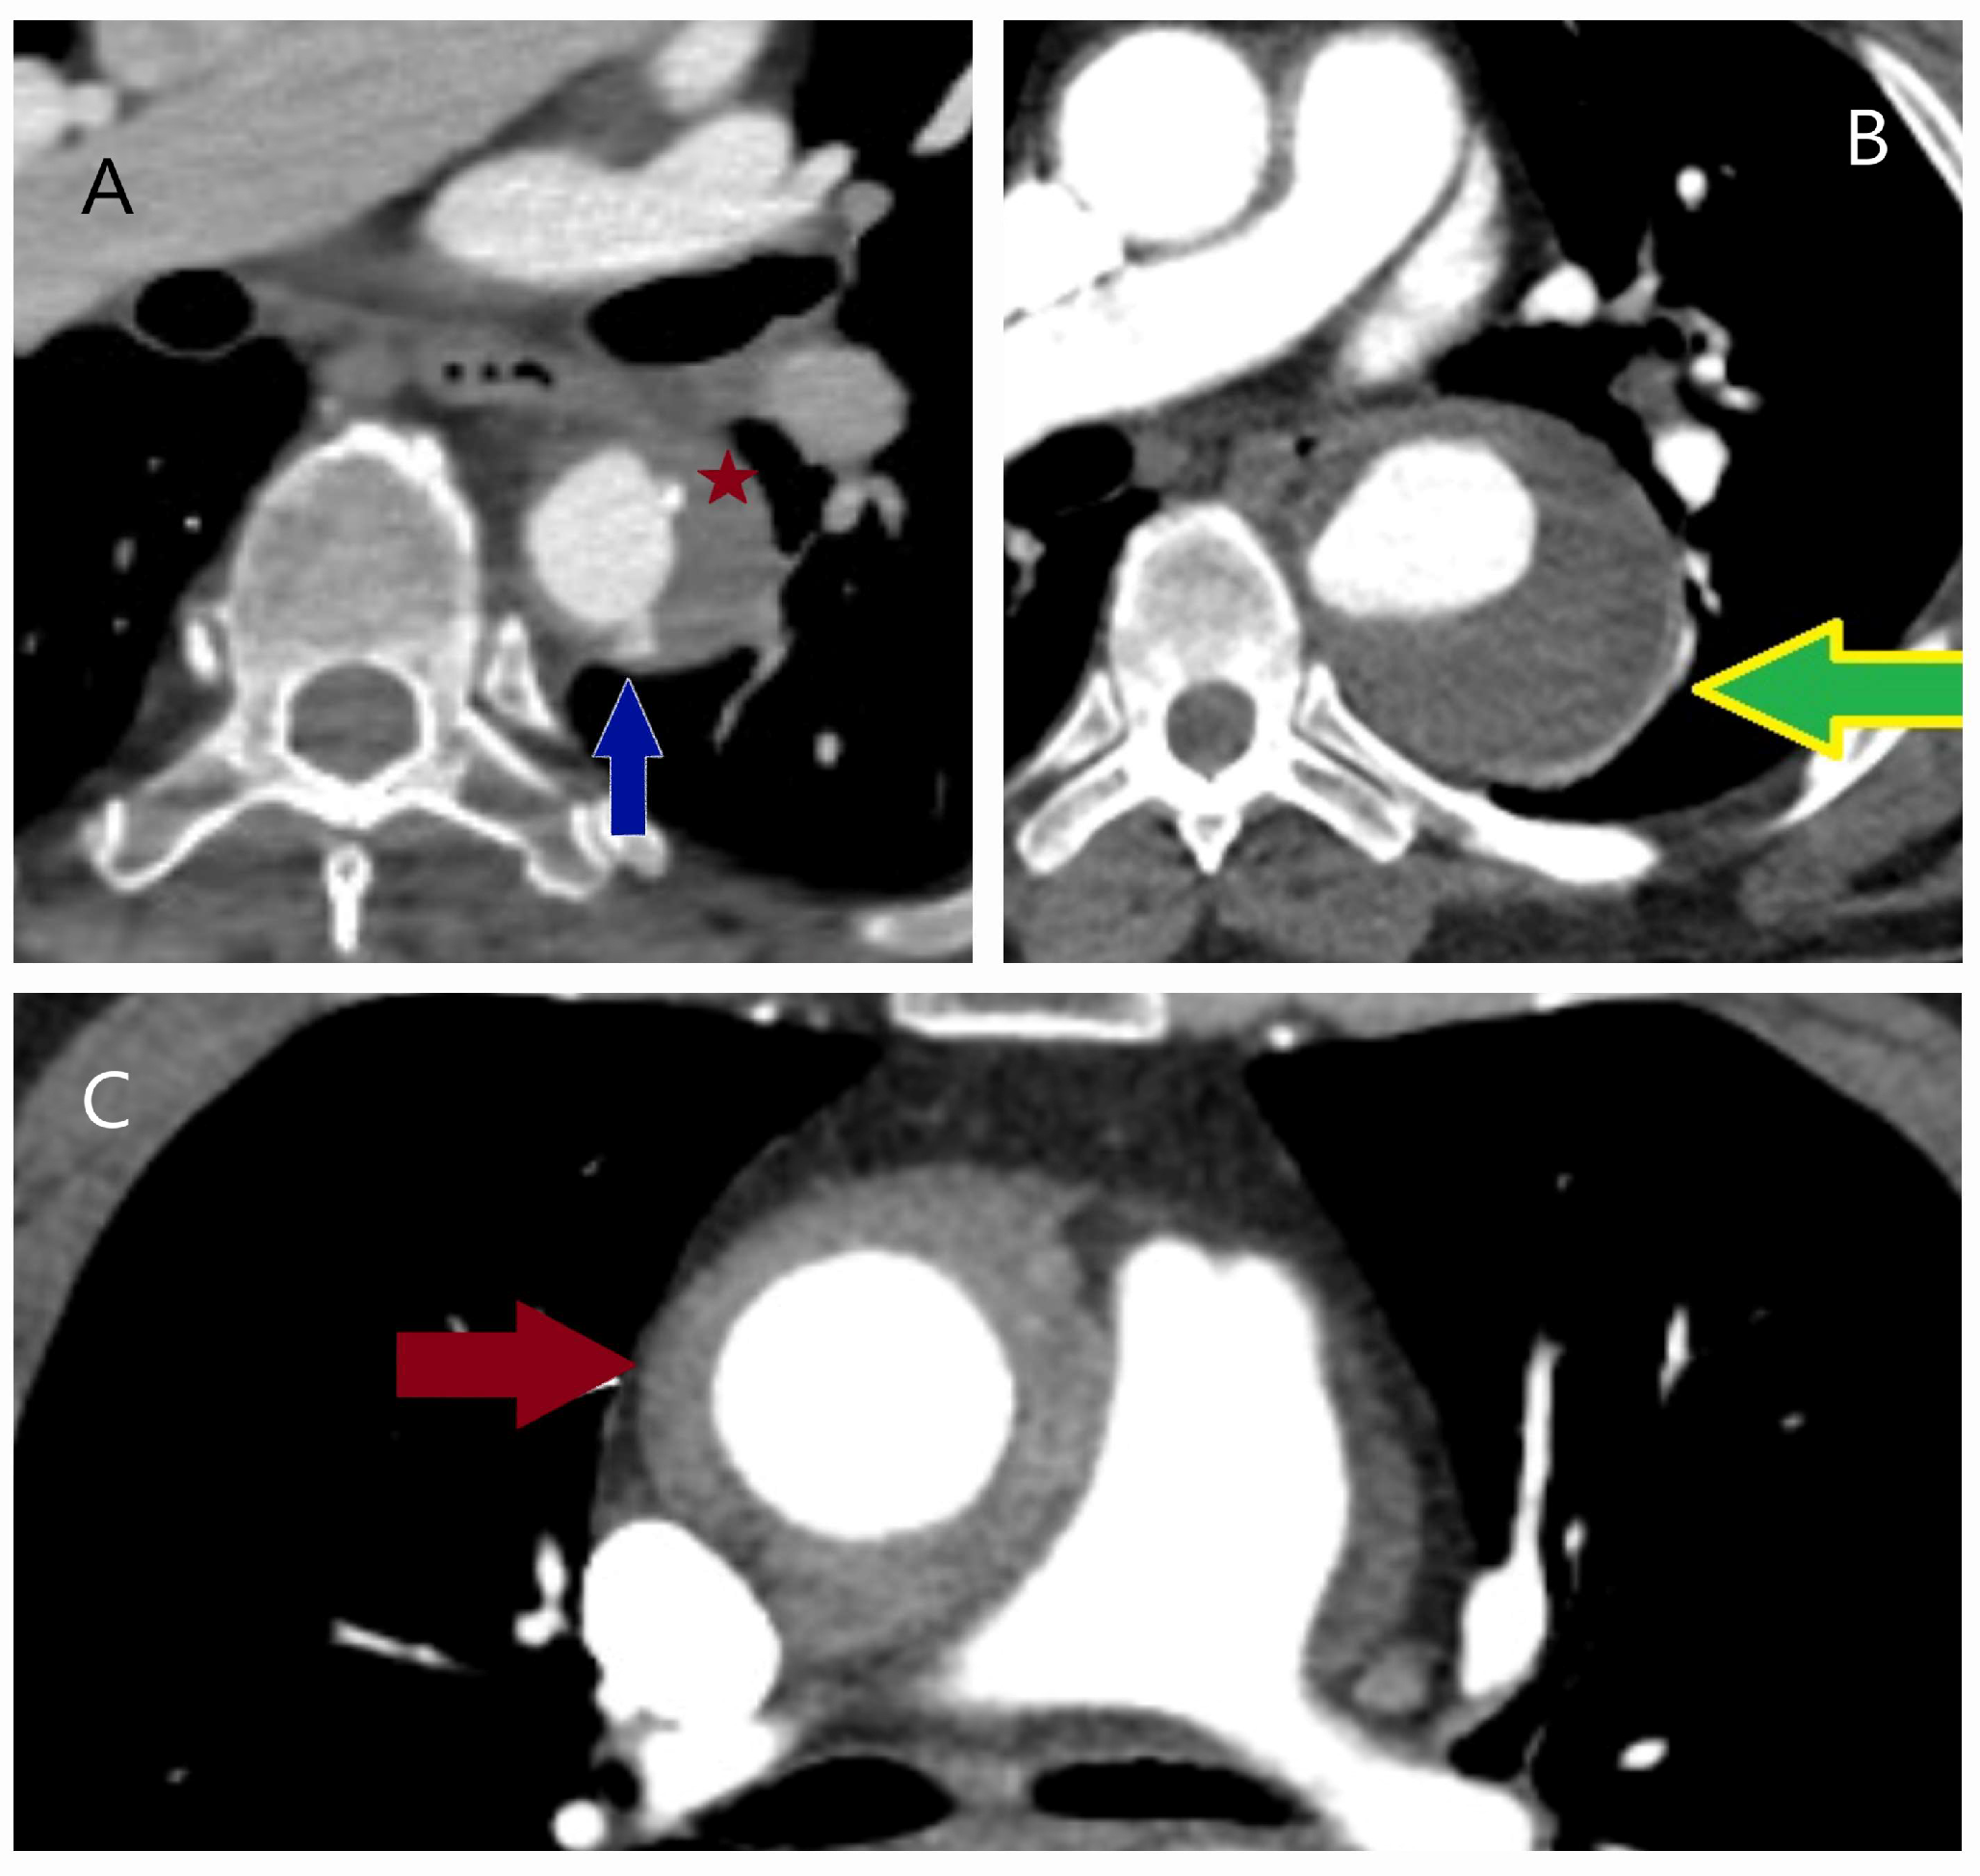

5.2.3. Computed Tomography